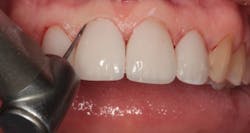

By carefully removing the veneers with fine diamond burs in a high-speed handpiece with water spray, I was able to minimize additional tooth structure removal, and no anesthetic was needed. Figure 3 shows the facial view after removal of the veneers. The incisal view can be seen in Figure 4. The patient decided that she wanted two additional veneers for her second premolars. Final impressions were taken, as well as a facebow record and occlusal registration. The patient chose Vita OM2 bleach shade as her desired color.

Figure 3: Facial view after removal of the veneers